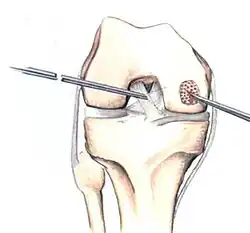

Intact lesions

If non-surgical measures are unsuccessful, drilling may be considered to stimulate healing of the subchondral bone. Arthroscopic drilling may be performed by using an antegrade (from the front) approach from the joint space through the articular cartilage, or by using a retrograde (from behind) approach through the bone outside of the joint to avoid penetration of the articular cartilage. This has proven successful with positive results at one-year follow-up with antegrade drilling in nine out of eleven teenagers with the juvenile form of OCD,[53] and in 18 of 20 skeletally immature people (follow-up of five years) who had failed prior conservative programs.[54]

The three methods most commonly used in treating full thickness lesions are arthroscopic drilling, abrasion, and microfracturing.